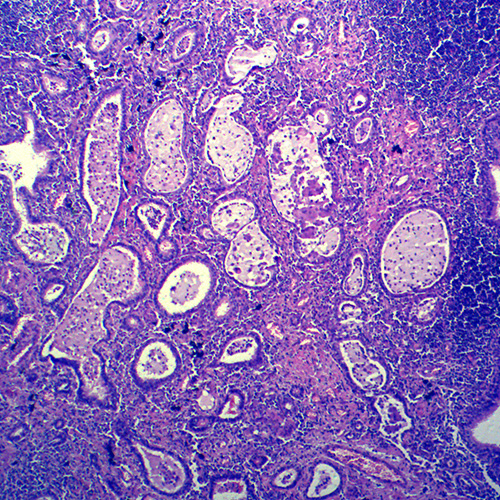

人体病理切片,炎症病理玻片,炎症病理玻片价格

浙江人体肿瘤病理玻片